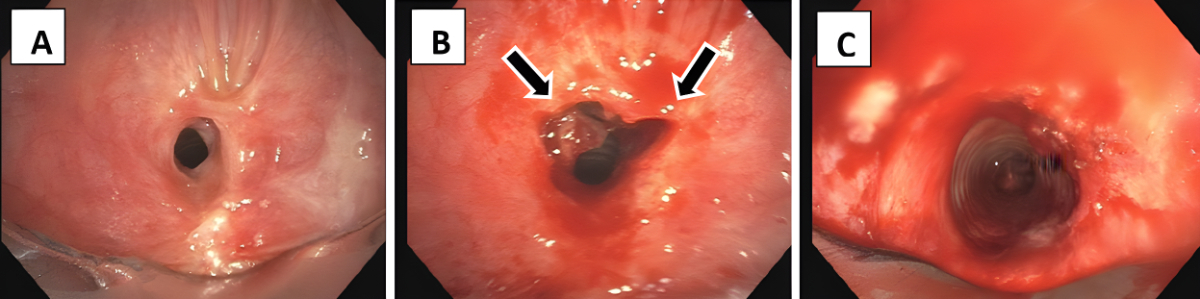

Endoscopic tracheoplasty was performed under general anaesthesia as an inpatient procedure. After the induction of total intravenous anaesthesia and muscle relaxation, the patient’s trachea was intubated with a rigid tracheoscope (Karl Storz SE & Co. KG, Tuttlingen, Germany),whereas the tip of the scope was placed between the vocal cords and stenosis using 4.5 mm, 0° Hopkins®optics (Karl Storz SE & Co. KG). After initiation of high-frequency jet ventilation, a flexible videobronchoscope (190 series,Olympus,Tokyo, Japan) was introduced into the tracheoscope and the web-like stenosis was cut radially at two defined locations at 10 and 2 o’clock (figure 1) with an electric papillotomy needle (MTW Endoskopie, Wesel, Germany), which was inserted over the working channel of the bronchoskope, and Endo-cut (VIO® 200D, APC 2, Erbe, Tübingen, Germany; effect 4, 40–50 W). Then the stenosis was dilated using rigid tracheoscopes with gradually increased diameter. Since 2016, 20–40 mg triamcinolone acetonide (Kenacort®, Dermapharm AG, Hünenberg, Switzerland) has been administered topically into the former stenotic area to prevent early recurrence due to scarring. In addition, from 2020, inhaled budesonide 200 µg bid has been initiated after hospital discharge to prevent recurrence (Pulmicort® Turbuhaler®, AstraZeneca, Baar, Switzerland). Since this is an uncontrolled single-arm study, the recurrence rate after sole tracheoplasty was historically compared to tracheoplasty including local triamcinolone administration without and with subsequent inhaled budenoside.

Figure 1The web-like stenosis before endoscopic intervention (A), when it was cut radially at two defined locations at 10 and 2 o’clock(arrows) (B) and after dilation using rigid tracheoscopes with gradually increased diameter (C).